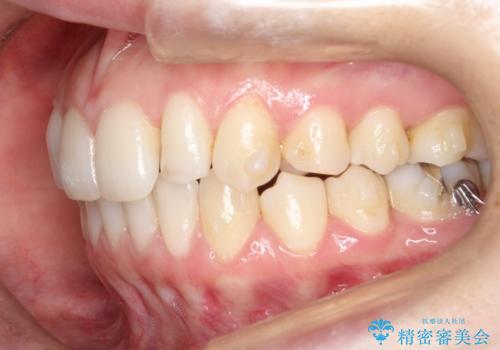

初診時の歯並びの状態としては、上下ともに前歯部の中等度のがたつきがあり、特に左上の前歯が1本内側に入り込んでしまっている状態でした。

また、2mm程度の正中離開がありました。